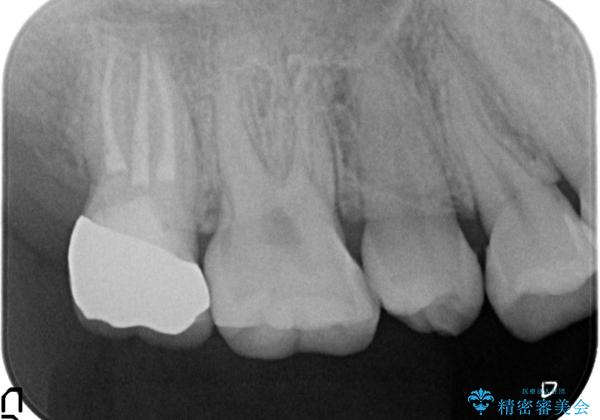

- 他院にて右上7番目の歯の根管治療を行ったが鈍い痛みが治まらないので診て欲しいといらっしゃった方の症例です。

再根管治療を行い症状の消失を確認後、オールセラミッククラウンによる補綴を行いました。

今回用いたオールセラミッククラウンはジルコニアフレームという白い素材の上にセラミックを盛っているため、審美性が非常に高いのが特徴です。

また、ジルコニアは人工ダイヤモンドの材料にも使われているほど高い強度を持っており、そのためオールセラミッククラウンは審美性だけでなく、奥歯やブリッジの補綴も可能とするクラウンです。